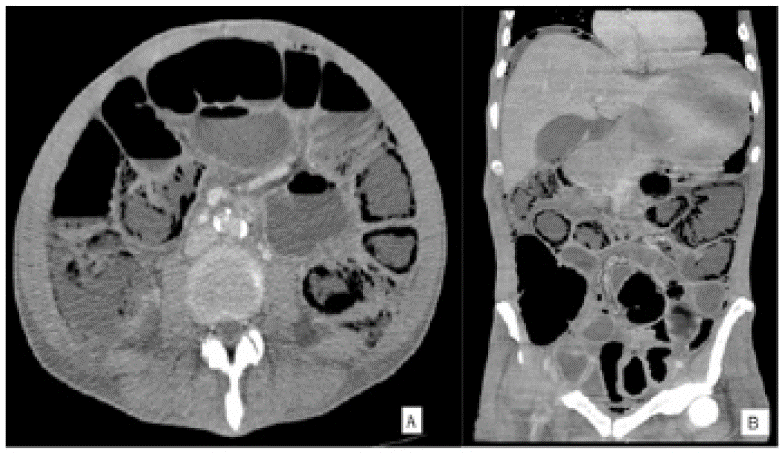

Ante la poca mejoría de los síntomas con el tratamiento médico se solicitó tomografía de abdomen (figura 1) en la que se observaron múltiples imágenes quísticas, redondeadas, localizadas en la pared del intestino delgado asociadas a ligero engrosamiento parietal del yeyuno, neumoperitoneo y líquido libre intra-abdominal. No se visualizaron alteraciones de las estructuras vasculares, pileflebitis ni neumobilia.

Puede darse de forma asintomática 11,13,14 o presentar síntomas inespecíficos 13,14 como diarrea, secreción de moco, dolor, distensión abdominal 11 y sangrado rectal 14. Hasta 58 % de los casos pueden ser evidentes en la radiografía de abdomen, teniendo 42 % de estos neumoperitoneo como hallazgo principal 12. En la tomografía se observan quistes con contenido aéreo 12 dependientes de la pared intestinal, como en los casos descritos.

El método más sensible para su evaluación es la tomografía 8,9. Se han descrito varios patrones como: lineal, curvilíneo y redondo 1,2,8,9, pudiendo haber un solo patrón o una mezcla entre estos 2. El aire puede estar localizado o distribuirse de manera difusa a lo largo de un asa intestinal 1. Por lo general, las burbujas de aire no desaparecen cuando se llega a un sitio donde hay un nivel gas-líquido 1.

El patrón que más se ha asociado a enfermedad benigna es el patrón circular (quístico) 2,7,8, el cual es mas común en el colon y está descrito en neumatosis intestinal quística 2,9,14. Por el contrario, el patrón lineal fue descrito por Kernagis et al. cuando ocurre infarto transmural 2 (figura 3) y está relacionado en el tipo secundario 7. El patrón curvilíneo también se ha relacionado mas con formas severas 8.